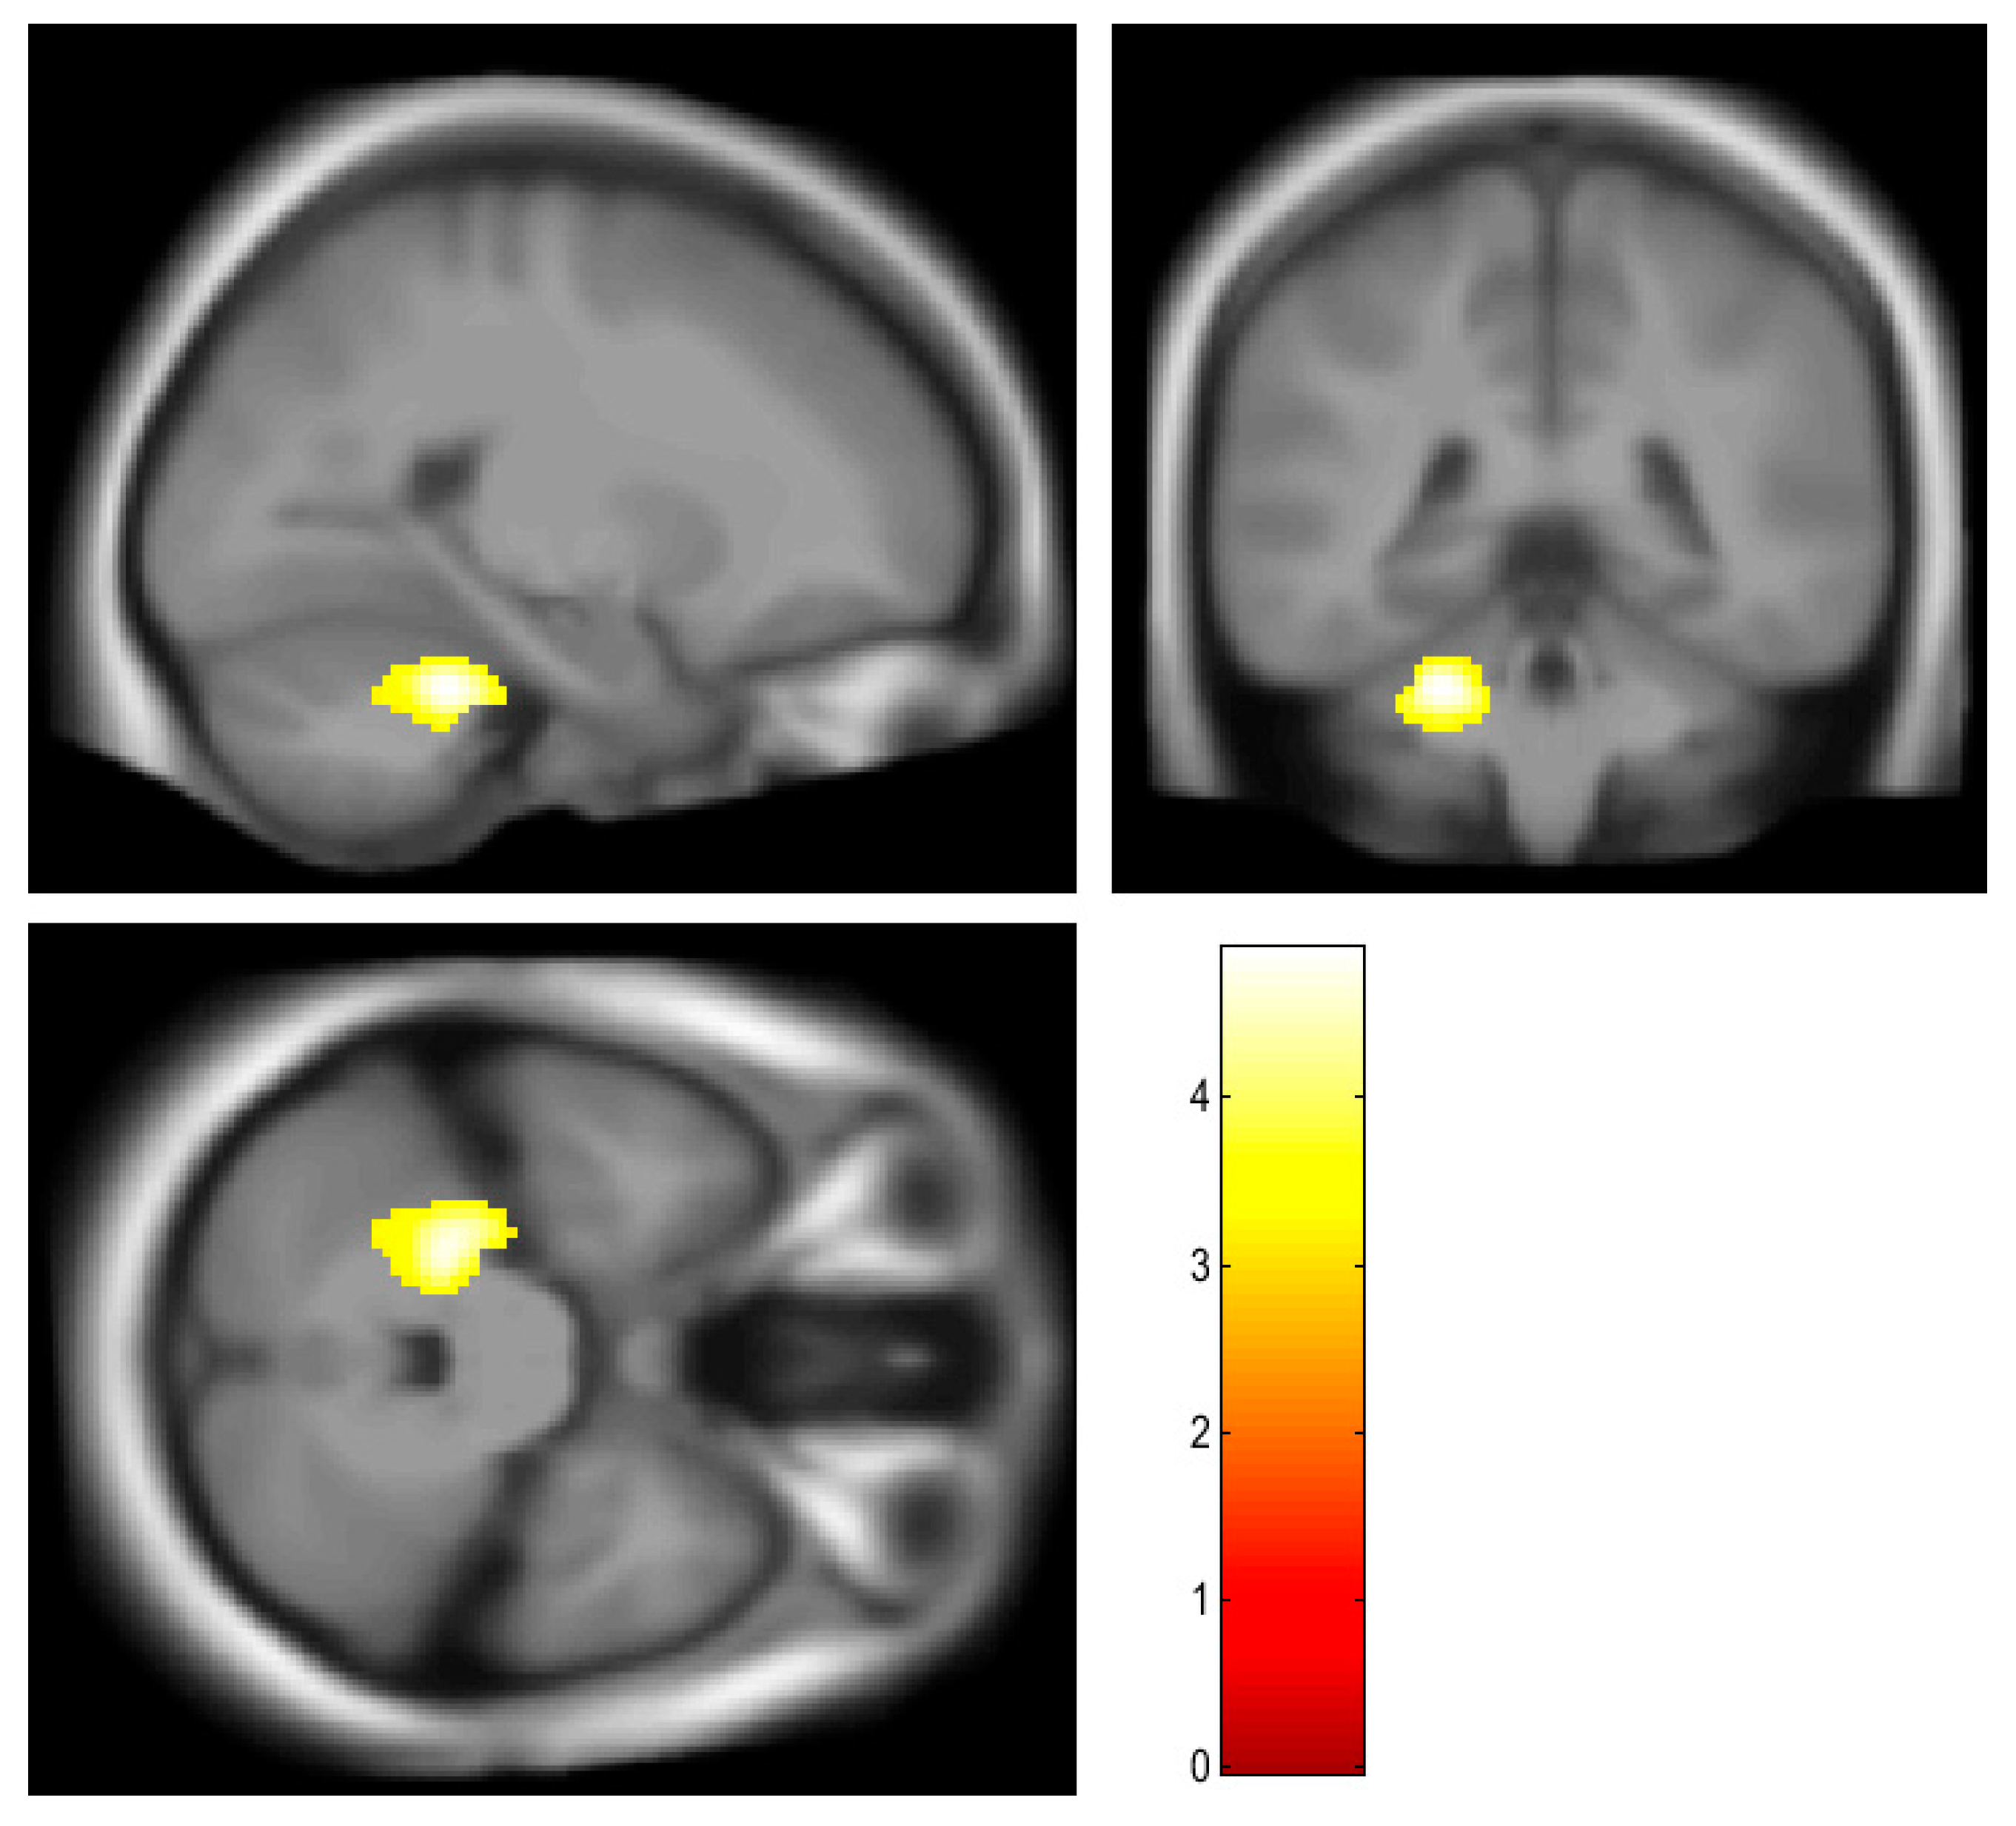

| Right cerebellum, anterior lobe | 521 | 6.55 | <0.001 | 28, −48, −30 |

| Left cerebellum, anterior and posterior lobe | 522 | 6.19 | <0.001 | −30, −50, −30 |

| Left cerebellum, anterior lobe | 458 | 4.87 | 0.009 | −24, −40, −30 |